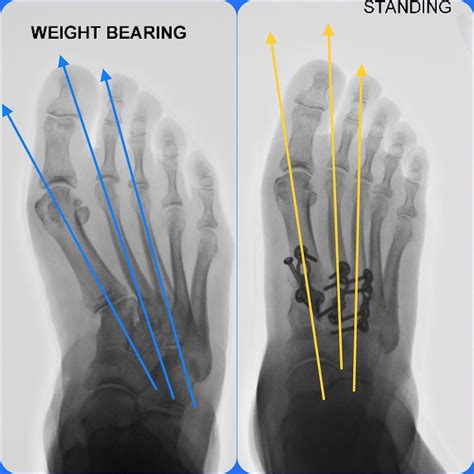

Diagnosing Metatarsus Varus Adductus

Diagnosing Metatarsus Varus Adductus typically involves a physical examination by a healthcare provider. The doctor will assess the child's gait, foot alignment, and range of motion. In some cases, imaging tests such as X-rays or MRI scans may be ordered to rule out other conditions or to assess the severity of the deformity.